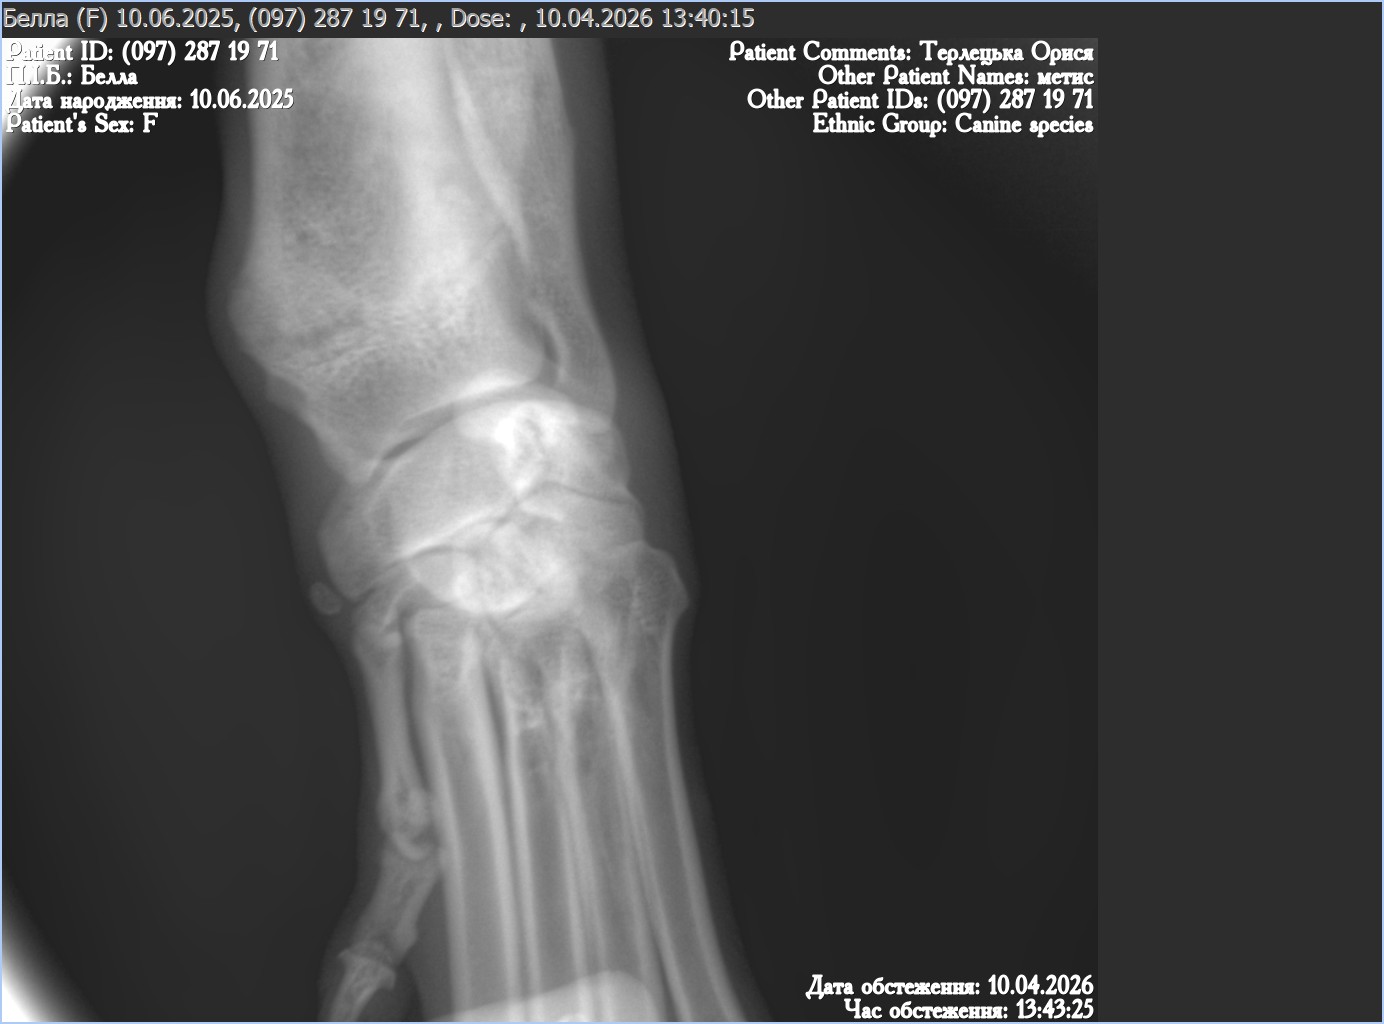

Unfortunately in December, when Bella was already ready to travel and even had a family waiting for her in England, Bella broke her front paw. The bone has healed well, however her front left leg remains slightly crooked. A recent follow-up X-ray confirmed that the bone itself healed correctly (see recent X-Ray).

The orthopaedic specialist explained that X-rays do not show ligaments, and it is very likely that a ligament injury was missed at the time of trauma. Unfortunately, as more than four months have now passed, this cannot be corrected. Surgery would be very complex, invasive, and would not guarantee a long-term improvement, therefore it was not recommended.

Most importantly — this does not affect Bella’s quality of life in any way. She has no pain, no restriction in movement, no discomfort, and lives a completely normal, active, happy life. The slight crookedness is now simply cosmetic, and may even become less noticeable over time.

Bella is vaccinated, microchipped and spayed. She previously suffered a broken front paw. The bone has healed well, but due to a likely past ligament injury, her front left leg remains slightly crooked. This is cosmetic defect, does not cause pain or discomfort, does not require treatment, and does not affect her activity or quality of life. Surgery was not recommended by an orthopaedic specialist.